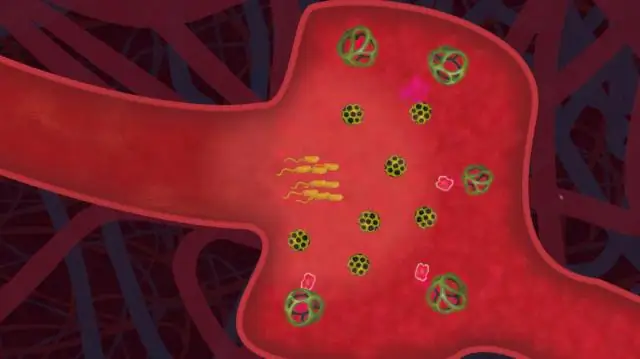

Микробы имеют реальный шанс распространения только при отсутствии гигиены: Они могут размножаться только в том случае, если некоторые из них, минуя все барьеры, установленные чистотой, попадают в пищу и затем - без стерилизации, пастеризации или иным образом ликвидированы тем временем, чтобы быть - в конечном итоге проглоченными людьми. Достигнув места назначения, большинство микробов все равно умирают, подвергаясь нападению и поражению бдительными клетками иммунной системы. Остальные умрут самое позднее, когда инфицированная человеческая жертва по совету знающего врача, которому она доверяет, перейдет на антибиотики.

Листериоз, атака бактерии Listeria monocytogenes, обычно заканчивается у людей до того, как может нанести непоправимый ущерб, но, к сожалению, не всегда. У беременных женщин, маленьких детей или людей с ослабленной иммунной системой он может вызвать лихорадку, рвоту или такие заболевания, как менингит, и до 20 процентов инфицированных даже умирают в результате инфекции.

Во-первых, исследователи генетически встроили ген светового маркера в представителей штамма Listeria, чтобы иметь возможность оптически проследить путь отдельных микробов в организме живой мыши, зараженной им, тщательно и с точечная точность. Как и ожидалось, бактерии сначала распространились в брюшной полости мышей, и в конце концов иммунная система нейтрализовала их практически за ночь - всего через 18 часов.

Очевидно побежден, потому что через несколько дней большее количество бактерий, которые, как считалось, были побеждены, внезапно снова стали видимыми: в большом количестве сконцентрировались в желчном пузыре мышей. Он представлял собой идеальное убежище для выживших среди бактерий, поскольку исследователи подозревают, что антитела и иммунные клетки не попадают сюда в больших количествах.

Теперь безопасное убежище могло бы только отсрочить конец листерии, если бы бактерии в желчном пузыре не развили внезапно некоторые особенности, несвойственные их виду. Как выяснили Контаг и его коллеги, листерии, которые обычно живут только внутри клеток тела своего хозяина, переносят свою деятельность на внеклеточные области желчного пузыря. Они также активируют гены, которые, по-видимому, позволяют им справляться с солями желчных кислот в новой среде. И: Внезапно внеклеточный патоген даже размножается в желчном пузыре и образует длинные цепочки бактерий в последовательных делениях, которые на самом деле считаются совершенно нетипичными для Listeria.